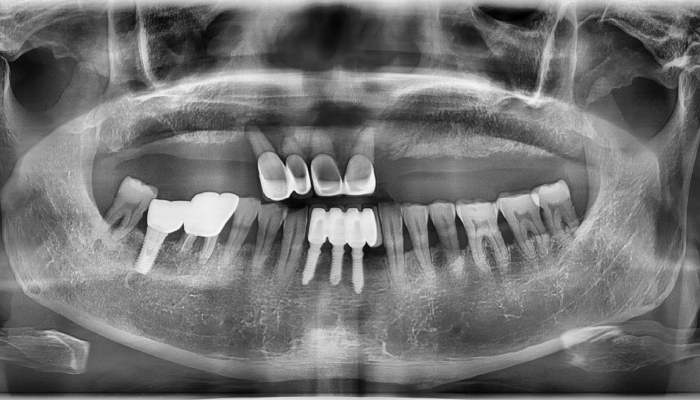

임플란트 | 내비게이션 임플란트 수술

환자명 남OO 치료기간 8주 한줄 설명 식립갯수 : 10개

• 식립갯수 : 10개